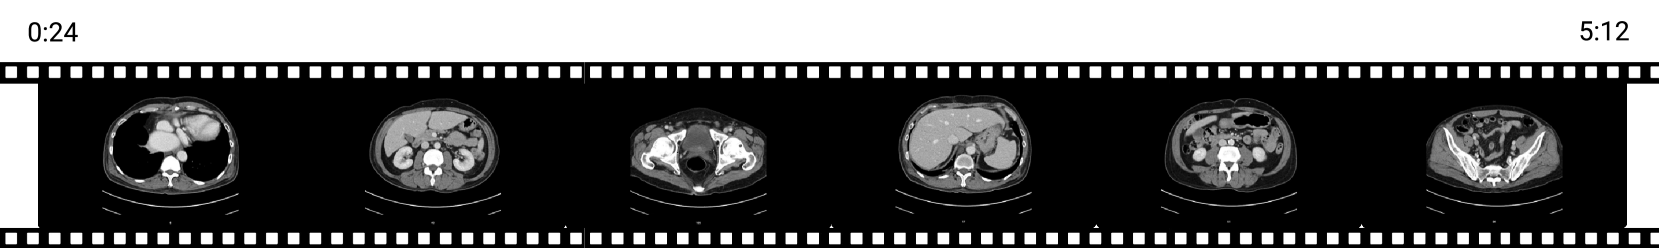

Figure 2 shows the distribution of our fine-tuning dataset, which comprises 22,668 video clips totaling 1031.6 hours of biomedical content. Most videos are under 5 minutes long, with an average length of 2 minutes. In total, we generated 79,367 Q/A pairs, averaging 3.5 Q/A pairs per video clip. The most common video modalities include ultrasound (231.8h), CT imaging (201.6h), and surgical and procedural (136.0h).

Similarly, the predominant anatomical regions in our fine-tuning dataset are the cardiac system (172.3h), gastrointestinal system (161.9h), musculoskeletal system (126.2h), and cranial and nervous system (114.9h). Appendix Figure 7 presents the resolution distribution of the fine-tuning dataset.